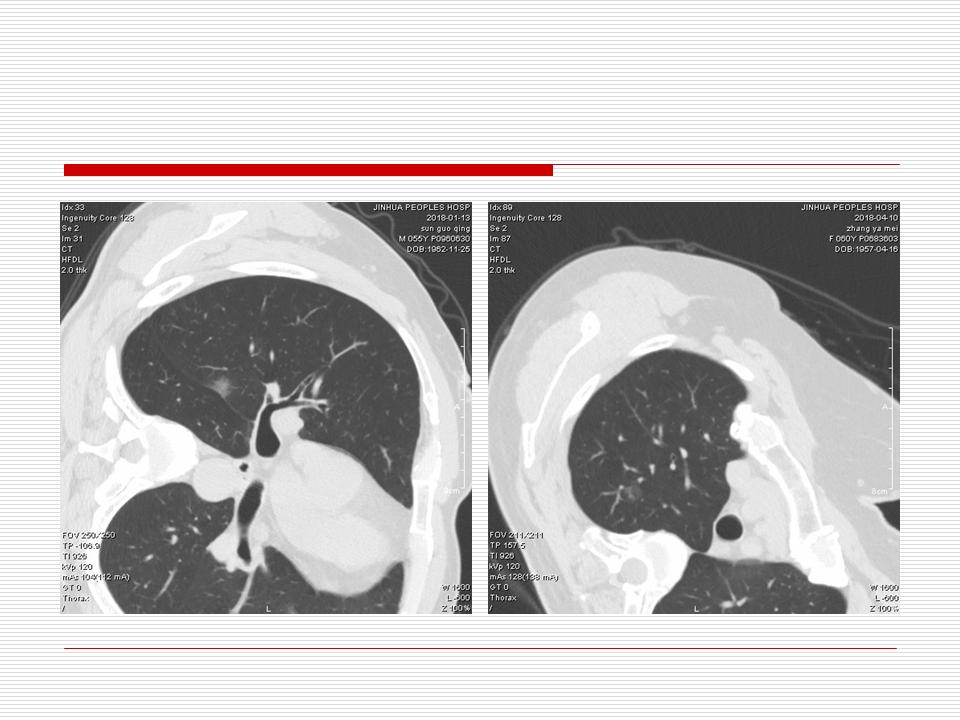

肺部阴影永恒且最重需要鉴别的是:到底是炎症还是肿瘤?但临床的病例中的影像表现难以界定或有些肿瘤特征,同时又有些炎症特点是非常常见的情况。作为临床医生我们怎么去总结分析,并找到之所以是炎症或之所以是肿瘤的细微差别或特点非常重要,也非常有用。2019.12.7浙江省2019年胸心外科学学术年会在宁波召开时,我的临床病例分析与经验总结<那些像肺癌的炎症与像炎症的肺癌>获得在大会交流的机会,以下为该PPT的内容,与你分享,希望对同道有益,有借鉴与启迪。若有探讨与进一不完善的建议,欢迎文末留言讨论: